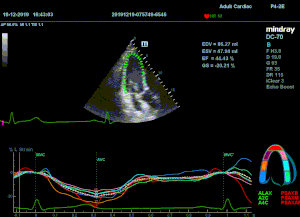

Как работать с данным методом? Для Longitudinal Strain необходимо записать видео петли апикальных сечений в память прибора: 4С, 3С, 2С. Для повышения качества трекинга рекомендуется производить запись на выдохе пациента. Затем произвести разметку по линии эпикарда, перикарда и центра миокарда. Нажатием кнопки «начать слежение» активируется программный алгоритм, видео петля оживает вместе с размеченными точками-speckle’ами. При необходимости производится коррекция. После анализа всех трех сечений можно получить данных продольной деформации как в среднем значении, так и по каждому сегменту миокарда левого желудочка. Нормальным показателем считается Longitudinal Strain -20%. Нижней границей -14%.

Видео примеры на приборе Mindray DC 70